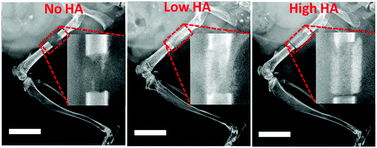

Stem cell-based tissue engineering for large bone defect healing has attracted enormous attention in regenerative medicine. However, sufficient osseointegration of the grafts combined with exogenous stem cells still remains a major challenge. Here, we developed a material approach to modulate the integration of the grafts to the host tissue when exogenous bone marrow stromal cells (BMSCs) were used as donor cells. Distinctive osseointegration of bone grafts was observed as we varied the content of hydroxyapatite (HA) in the tissue scaffolds implanted in a mouse femur model. More than 80% of new bone was formed in the first two weeks of implantation in high HA content scaffolds but host integration was poor, while only less than 5% of the new bone was formed during this time period in the No HA group but the host integration was good. Cell origin analysis leveraging the GFP reporter indicates new bone in the HA containing groups was mainly derived from donor BMSCs. In comparison, both host and donor cells were found on the new bone surface in the No HA groups which led to seamless bridging between host tissue and the scaffold. Most importantly, host integration during bone formation is closely dictated by the content of HA present in the scaffolds. Taken together, we demonstrate a material approach to modulate the osseointegration of bone grafts in the context of an exogenous stem cell-based bone healing strategy which might lead to fully functional bone tissue regeneration.